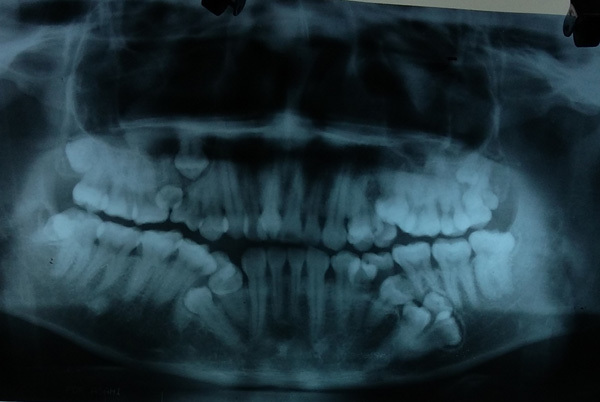

Theo BS Nguyễn Thanh Thái, Trưởng khoa Phẫu thuật Tạo hình Hàm mặt, sau khi chỉ định chụp CT, panorama, các bác sĩ lại tiếp tục phát hiện thêm bệnh nhân có 4 mầm răng chưa mọc.

Hình ảnh trên phim chụp cho thấy, ngoài 13 răng đã mọc, bệnh nhân còn 4 mầm răng khác chưa nhú |

"Hiện tượng mọc thừa răng không phải chuyện lạ, tuy nhiên bình thường chỉ thừa 1-2, nhiều lắm thì 3 chiếc. Trường hợp nhiều nhất chúng tôi từng gặp là thừa 8 răng nhưng trường hợp thừa 17 răng như anh Sơn thì chưa từng gặp”, BS Thái nói.